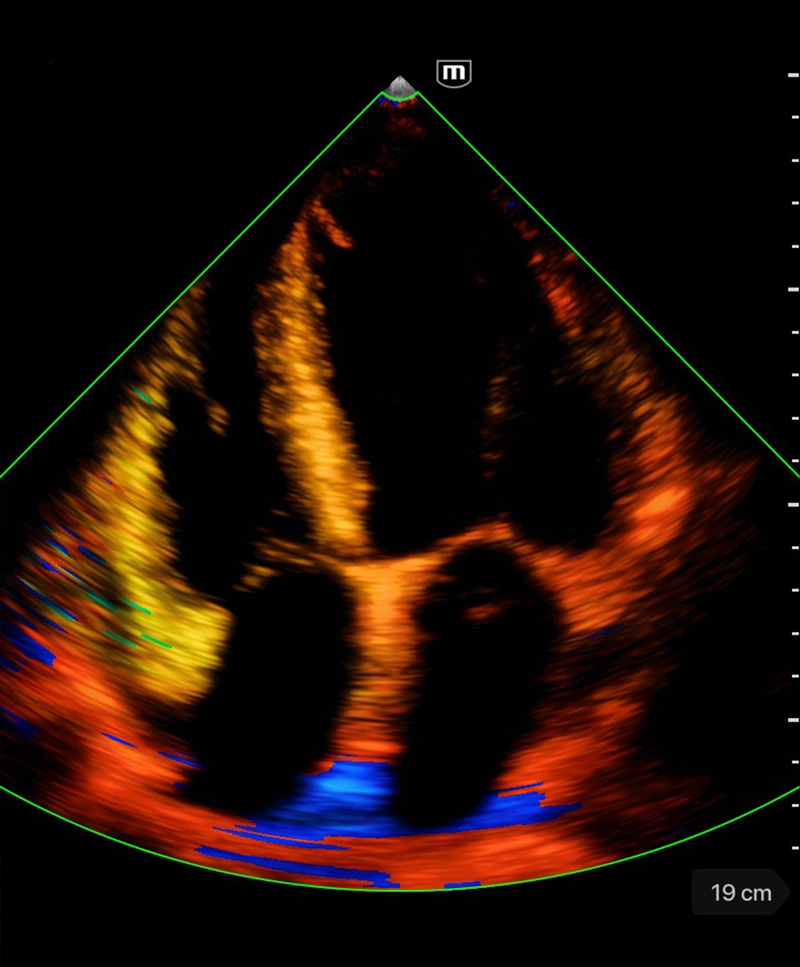

Clinical Images

Tissue Velocity Doppler

Clinical Images

Tissue Velocity Doppler